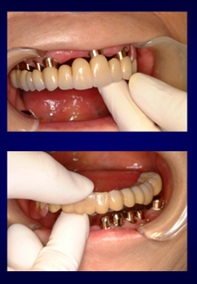

ケース1:右下奥歯3本を失った70代女性

当初は保険のクラスプ義歯を入れていましたが、動いて痛く、しっかり噛めないという訴えがありました。インプラントは希望されなかったため、テレスコープ義歯に変更。結果として右側でも硬いものが噛めるようになりました。写真の左は外したところ、右は装着したところです。手前2本の歯に内冠を作り、セメントでかぶせてあります。

この内冠に合わせて外冠が作られ、外冠の内面にはPEEK(ポリエーテルエーテルケトン)という耐久性の高い樹脂が貼られています。これが維持装置として働きます。